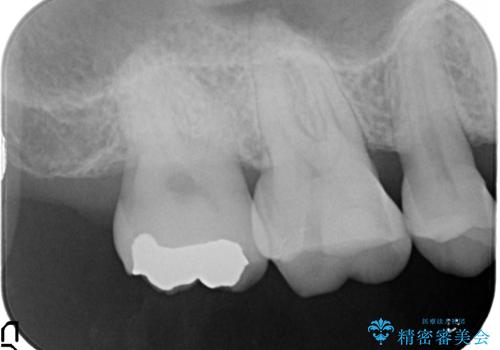

- 以前治療したところが欠けてしまったところを見てほしいとのことで来院されました。

右上の後ろから2番目の歯に詰めてあったものが、一部欠けてしまっていました。

そして隣接部にも虫歯が確認されました。

ゴールドインレーにて治療することとなりました。